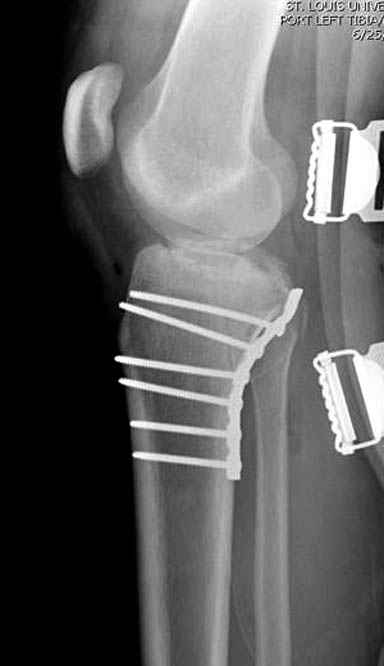

Трудно поверить, что разрекламированная Ортопедическая школа Восточной Украины позволяет такие странные снимки? На прямом снимке сохранен общий контур плато, но не известна судьба импрессии суставной поверхности. На полубоковой?, оставлен без репозиции задне-медиальный отдел, и навряд ли после такой фиксации можно удовлетвориться результатом.

Такая ситуация характерна для многих, когда принимается ошибочное решение, т.е пытаются фиксировать одним имплантом переломы двух мыщелков. Латеральная пластина приемлема только для тех случаев, когда сохраняется интактным медиальный диафизарный кортекс и отсутствует фрагментация на верхушке медиального перелома.

При сложных переломах тибиал плато для своего рода Damage Control мы иногда применяем поэтапную тактику. Сперва оперируется одна сторона, а потом после рекондиции мягких тканей окончательный этап.

Если состояние мягких тканей позволяет, я бы предложил такой метод для вашего больного. Без предварительного планирования будет трудно, но шанс не надо упускать. Всего несколько дней после операции, и такая тактика лучше, чем недовольный молодой пациент.

Надеюсь, представленные снимки разных случаев помогут разобраться в тактике, и критика примется без личной обиды.